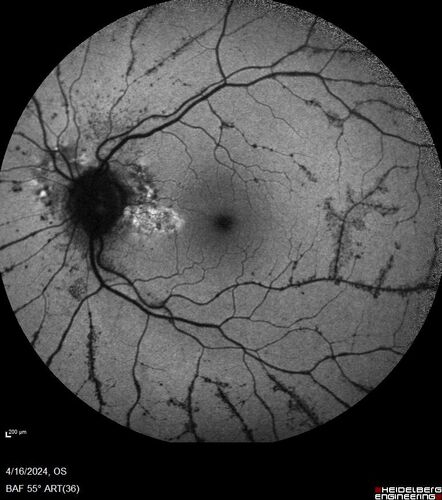

Posterior Pigment Dispersion Syndrome

81 year old man with cataract surgery 30 years ago and normal vision who had bilateral vitrectomy for dense floaters and has pigment on his IOL surface and all over the retina (but not on the cornea) VA 20/25 OU